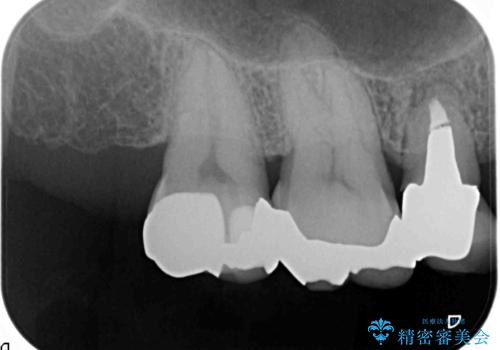

- 笑った時に口の中で目立つ金属を外したい、虫歯の治療を再発の内容しっかりと行って欲しいと希望され来院されました。

銀歯・虫歯を丁寧に除去したのち精密なセラミック治療を行うことで長期的な予後を目指します。

- 57万円(仮歯・ファイバーコア・ジルコニアクラウン×5)費用は治療当時の料金となります